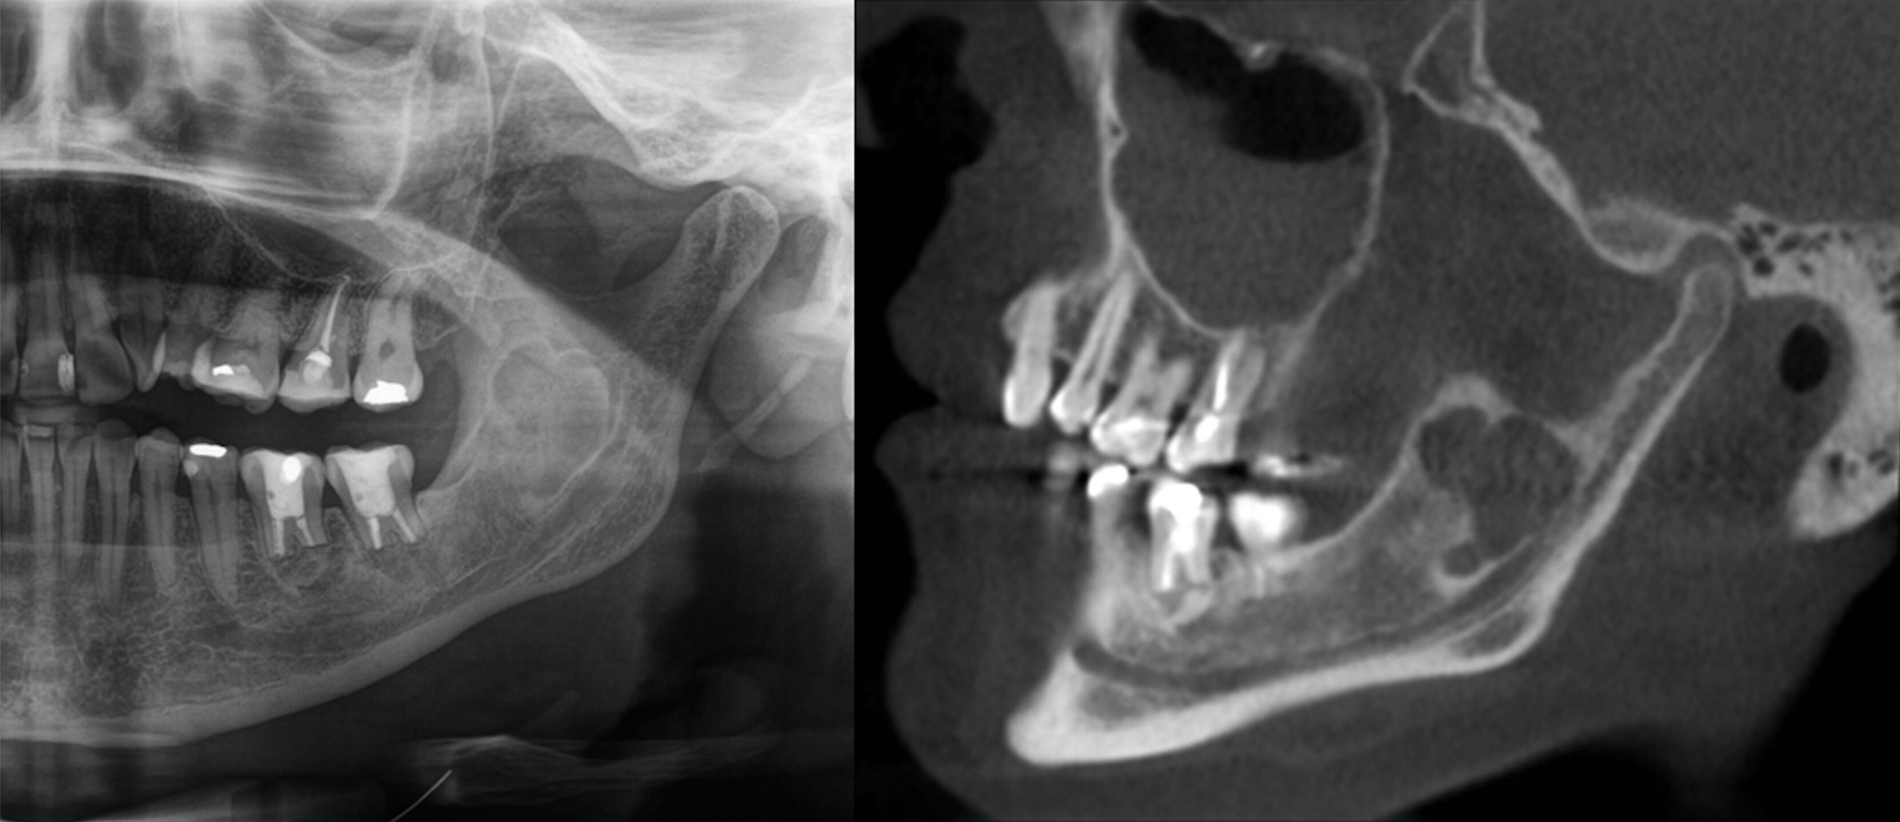

Die histopathologische Beurteilung des enukleierten Zystenmaterials bestätigte die Verdachtsdiagnose einer Keratozyste. Als sich zwei Jahre später im Rahmen der regelmäßigen radiologischen Nachkontrollen erneut eine zystenähnliche Struktur im Bereich des linken aufsteigenden Unterkieferastes demarkierte, wurde die Patientin zur weiteren Diagnostik und Therapie an unsere Klinik überwiesen. Eine zusätzlich angefertigte digitale Volumentomografie (DVT) der betreffenden Region (Abbildung 2) erhärtete den klinischen Verdacht eines Keratozystenrezidivs, so dass zunächst eine erneute Zystektomie in Intubationsnarkose durchgeführt wurde.